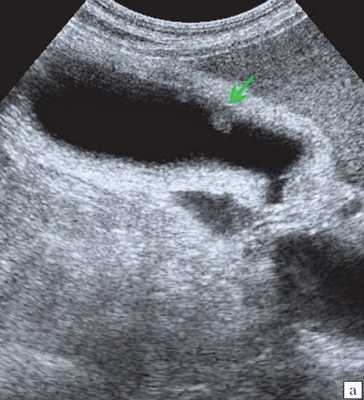

Ультрасонография является эффективным средством выявления полиповидной формы холестероза 4. Традиционной считается следующая сонографическая характеристика холестериновых полипов: неподвижные гиперэхогенные структуры, которые не дают акустической тени и прикрепляются к стенке желчного пузыря. Контуры таких образований, как правило, ровные, а размеры таких образований различны, чаще не превышают 10 мм (рис. 2).

![Эхограмма - одиночный полип в желчном пузыре (2а)]()

a) Одиночный полип в желчном пузыре (гиперэхогенное пристеночное неподвижное образование, с ровными контурами, без акустической тени).

Однако, по некоторым данным, размеры холестериновых полипов могут быть более 20 мм. Кроме того, полипы больших размеров (в 7% от общего числа) могут иметь пониженную эхогенность и фестончатый контур.

Мелкие холестериновые включения, образующие диффузную сеточку в толще подслизистого слоя размерами 1-2 мм, выглядят как локальное утолщение или уплотнение стенки желчного пузыря и в некоторых случаях (см. рис. 2) вызывают реверберацию (эхографический симптом "хвост кометы").